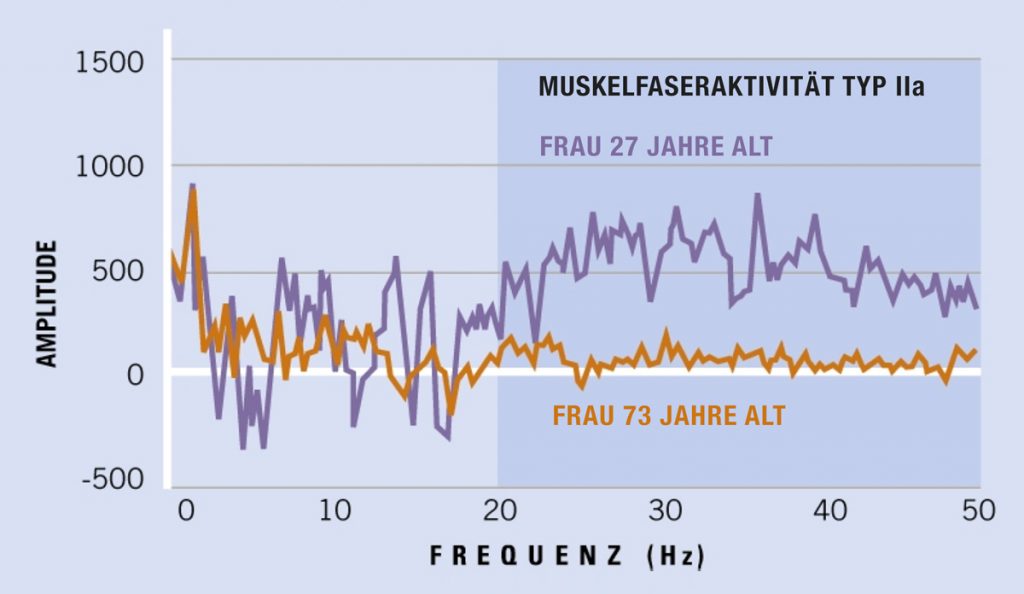

Bei einem Erwachsenen pumpt das Herz täglich etwa 6.000 bis 8.000 Liter Blut in die Blutbahn, in die Arterien. Die gleiche Menge Blut muss über die Venen zurück zum Herzen transportiert werden, wobei die Schwerkraft überwunden werden muss. Die Wadenmuskelpumpen drücken das Blut durch die Venen nach oben, während die Venenklappen den Rückfluss des Blutes nach unten verhindern und so der Schwerkraft entgegenwirken. All dies geschieht im gleichen Rhythmus wie das Herz, das Blut nach unten pumpt. Auch hier spielen die Muskelfasern vom Typ IIa eine entscheidende Rolle, um die Funktionsfähigkeit des Blutrückführungssystems zu ermöglichen: Bei einem gesunden Menschen, der gehen, laufen, Treppen steigen und mobil bleiben kann, werden die Wadenmuskelpumpe und die damit verbundenen Muskelfasern in den Waden stark gehalten und können die Venenfunktion stärken. Bei sehr inaktiven Menschen werden die Muskelpumpe und die Muskelfasern des Typs IIa geschwächt oder beeinträchtigt. Durchblutungsstörungen in den Beinen können die Folge sein. LiV verbessert die Durchblutung bereits nach wenigen Minuten. Die sanften Vibrationen aktivieren die Muskeln und erhöhen die Versorgung der Muskelfasern Typ IIa und der Wadenmuskelpumpe mit Nährstoffen und Sauerstoff. Eine kontinuierliche, regelmäßige LiV-Behandlung stärkt die Wadenmuskulatur und steigert ihre Fähigkeit, ihre Funktion des zweiten Herzens zu erfüllen.

Bei einem Erwachsenen pumpt das Herz täglich etwa 6.000 bis 8.000 Liter Blut in die Blutbahn, in die Arterien. Die gleiche Menge Blut muss über die Venen zurück zum Herzen transportiert werden, wobei die Schwerkraft überwunden werden muss. Die Wadenmuskelpumpen drücken das Blut durch die Venen nach oben, während die Venenklappen den Rückfluss des Blutes nach unten verhindern und so der Schwerkraft entgegenwirken. All dies geschieht im gleichen Rhythmus wie das Herz, das Blut nach unten pumpt. Auch hier spielen die Muskelfasern vom Typ IIa eine entscheidende Rolle, um die Funktionsfähigkeit des Blutrückführungssystems zu ermöglichen: Bei einem gesunden Menschen, der gehen, laufen, Treppen steigen und mobil bleiben kann, werden die Wadenmuskelpumpe und die damit verbundenen Muskelfasern in den Waden stark gehalten und können die Venenfunktion stärken. Bei sehr inaktiven Menschen werden die Muskelpumpe und die Muskelfasern des Typs IIa geschwächt oder beeinträchtigt. Durchblutungsstörungen in den Beinen können die Folge sein. LiV verbessert die Durchblutung bereits nach wenigen Minuten. Die sanften Vibrationen aktivieren die Muskeln und erhöhen die Versorgung der Muskelfasern Typ IIa und der Wadenmuskelpumpe mit Nährstoffen und Sauerstoff. Eine kontinuierliche, regelmäßige LiV-Behandlung stärkt die Wadenmuskulatur und steigert ihre Fähigkeit, ihre Funktion des zweiten Herzens zu erfüllen.